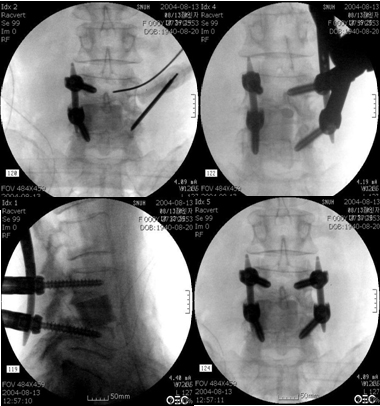

영상 가이드 사용: 플루오로스코피(실시간 X-레이) 또는 CT를 사용하여 나사못과 로드의 정확한 배치를 가이드합니다.

영상 가이드: 실시간 X-레이 또는 컴퓨터 단층촬영(CT) 영상을 이용하여 정확한 위치에 나사못을 삽입합니다.

나사못 삽입: 영상 가이드를 통해 정확한 위치와 각도로 나사못을 삽입합니다.

로드 삽입: 나사못들을 연결하는 금속 로드를 삽입하여 척추를 안정시킵니다.

마무리: 나사못과 로드의 위치를 확인하고 절개 부위를 봉합합니다.